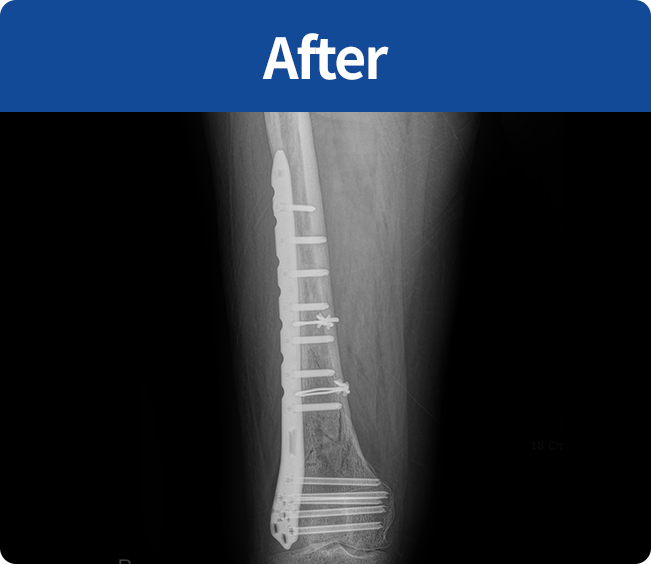

골절 고정술

부러진 뼈를 해부학적 위치로 정확하게 맞춘 뒤,

뼈가 안정적으로 붙을 수 있도록

금속판, 나사, 핀 등을 이용해

고정하는 수술(내고정술, 외고정술)

뼈가 안정적으로 붙을 수 있도록 금속판, 나사, 핀 등을 이용해 고정하는 수술

(내고정술, 외고정술)